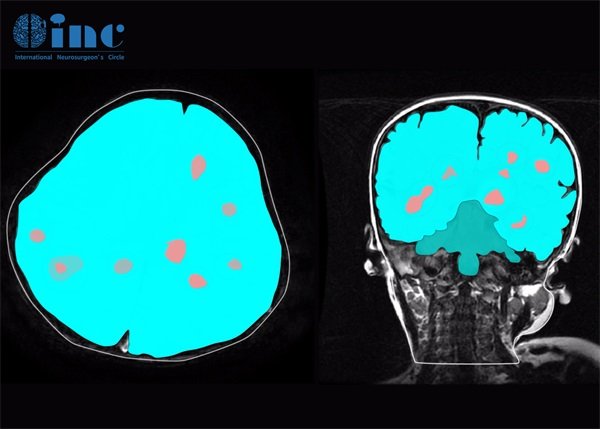

左颞叶海绵状血管瘤症状及会复发嘛?海绵状血管瘤的症状因个体差异和瘤体位置而异。左颞叶海绵状血管瘤是一种常见的脑部血管畸形,其症状可能包括头痛、癫痫发作、认知功能障碍等。虽然大部分患者可以在诊断后得到合理控制,但对复发的担忧仍然存在。复发是海绵状血管瘤患者关心的一个重要问题。虽然许多患者在治疗后能够获得良好的控制,但依然存在复发的风险。

海绵状血管瘤的症状因个体差异和瘤体位置而异。对于位于左颞叶的海绵状血管瘤,症状通常与大脑的特定功能区密切相关。

左颞叶海绵状血管瘤的复发可能受多种因素影响,如 肿瘤的大小、位置及治疗方式的选择。某些情况下,即使经过手术切除,残留肿瘤或出血也可能导致复发。